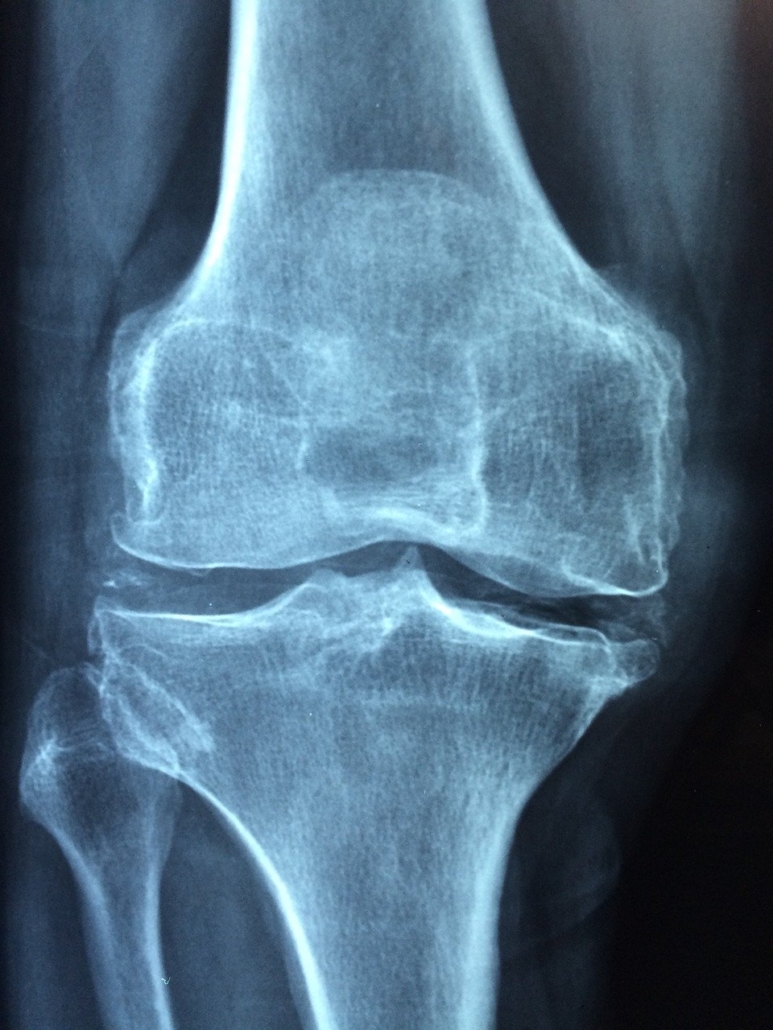

Arthrose / Arthritis

Bei der Arthrose handelt es sich um eine degenerative Gelenkerkrankung, die im Gegensatz zur Arthritis primär nicht entzündlich ist. Sie entsteht vor allem durch langjährige Überbelastung und zeichnet sich durch eine progrediente Veränderung der Knorpel- und Knochenstruktur aus, die schließlich zur Gelenkdeformierung führen kann.

Unter einer Arthritis versteht man eine Entzündung eines oder mehrerer Gelenke, die oft mit Gelenkschmerzen, Schwellung und Rötung einhergeht.